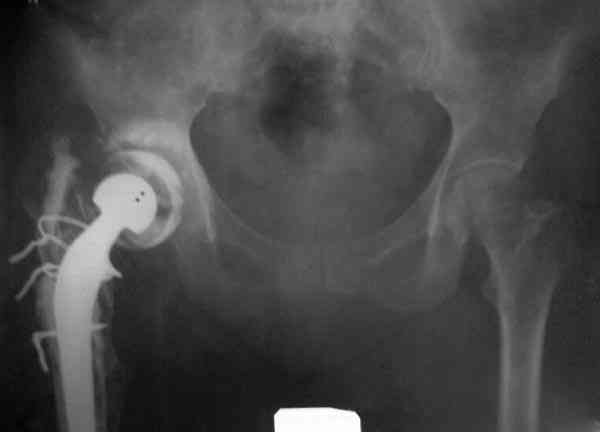

Представляю вашему вниманию снимки (прошу прошения за качество снимков) больной 48 лет с ревматоидным артритом, которой был сделан тотальный эндопротез справа,

контрольный снимок сделали только на 21день после операции (№1) и с интервалом 5 дней второй снимок (№2)

Судя по всему, произошел раскол наружной стенки бедра и ножка находится вне костного канала. В таком случае

решение одно - удаление ножки и установка новой в расчете на дистальную фиксацию. Конктреную модель подсказать тяжело из-за низкого качества Р-грамм.